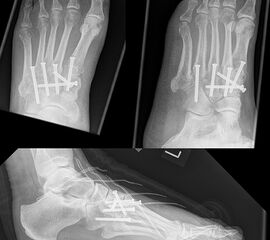

Wird die Entscheidung zur Arthrodese gefällt, sollten nur Gelenke mit einer symptomatischen Arthrose versteift werden. Meist genügt die Arthrodese der TMT-1 bis 3-Gelenke. Die Arthrodese kann mit Schrauben oder dorsalen Platten durchgeführt werden. Die betroffenen Gelenkflächen werden entknorpelt und das Gelenk mit einer Zugschraubentechnik oder einer dorsalen Platte stabilisiert (Abb. 19-22) 25 (Richter 2002; Richter 2007). Einige Autoren befürworten eine primäre Arthrodese auch bei rein ligamentären Verletzungen mit multidirektionaler Instabilität, da diese eine schlechte Heilungstendenz aufweisen und häufiger zu Korrekturverlust neigen 3617112.

Zum Lesen der Bildbeschreibung und zur Vollansicht bitte die Bilder anklicken.

Nach Lisfranc-Luxationen (Myerson-Klassifikation) erfolgt eine Ruhigstellung und Entlastung im Unterschenkelgips oder Walker für 6-8 Wochen. Anschließend wird nach Röntgenkontrolle in Abhängigkeit von der Knochenheilung ein schrittweiser Belastungsaufbau im Walker für weitere 6-8 Wochen durchgeführt. Nach erneuter Röntgenkontrolle 12-16 Wochen postoperativ kann meist auf einen Konfektionsschuh gewechselt werden. Unterstützend erfolgt eine Einlagenversorgung (Abb. 15). Nach Freigabe sollten sich eine differenzierte Physiotherapie zur Mobilisation der zuvor transfixierten Gelenke sowie eine Gangschule anschließen. Häufig besteht eine lange anhaltende Schwellneigung, die mit Kompressionstrümpfen und Lymphdrainage therapiert wird.